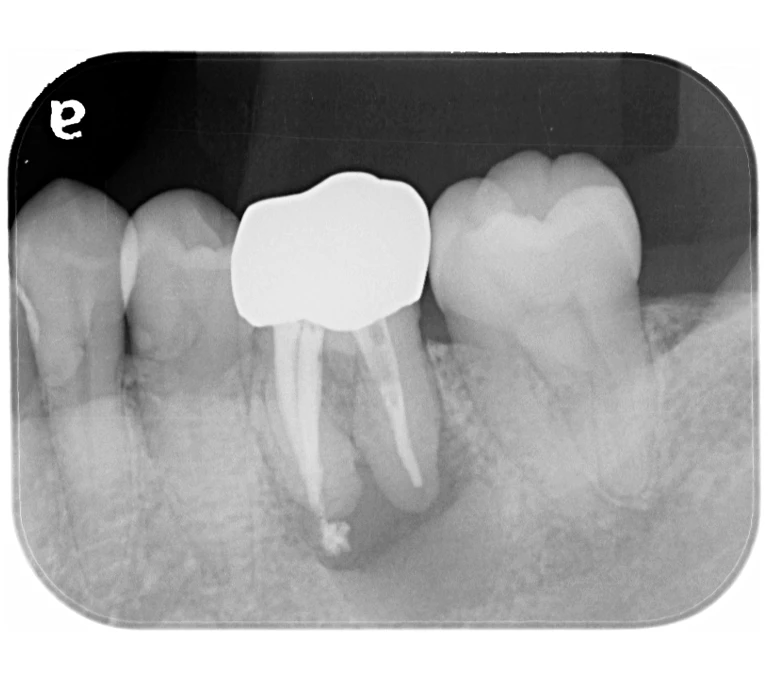

case 4.

治療前

治療後

| 主訴 | 右下奥歯が痛い。 他院で『膿の袋が大きいため抜歯』と言われセカンドオピニオン希望でご来院。 |

|---|---|

| 治療期間 | 約半年(6か月) |

| 治療費 | 約5万円 |

| 治療内容 | ラバーダム、マイクロスコープ下にて根管治療を実施し、歯根端切除を行う。歯茎の腫れは消失し違和感や痛みも消失した。 |

| 治療のリスク | マイクロスコープやCTを使用し、可能な限り精密な根管治療を行っていますが、歯根の形態や病変の大きさ、過去の治療履歴などにより、治癒が得られない場合があります。 また、治療後に再感染や歯根破折が生じることもあり、その場合は再治療や抜歯が必要となることがあります。 治療結果には個人差があり、すべての症例で同様の経過を保証するものではありません。 |